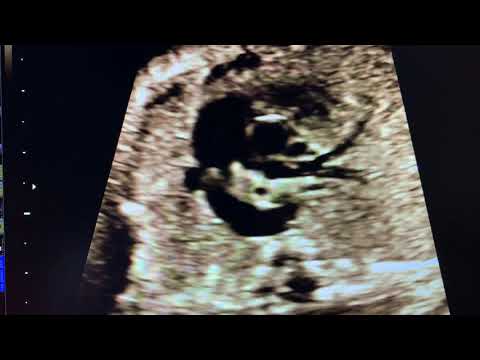

Persistent Left SVC by Dr Nitin Potdar